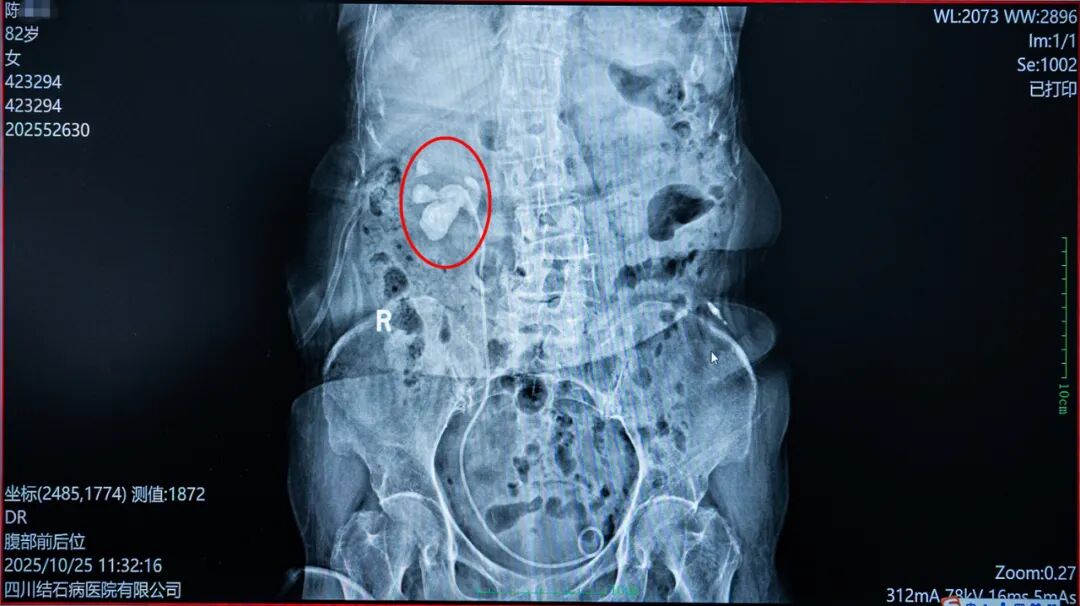

看着患者的检查报告,国际尿石症联盟IAU委员、四川十大外科名医、四川结石病医院泌尿外科带头人常立高教授判断,感染的元凶正是右侧肾脏内的那颗铸型结石。结石造成了尿路梗阻,尿液无法正常排出,导致肾积水日益加重,继而引发肾脏及周围组织严重感染。

△ 患者右肾内的结石

手术中,常教授先将此前置入的双J管拔出,随后通过输尿管软镜精准探查,在陈奶奶右肾中下盏发现了多颗结石,其中最大的一颗直径约5厘米。常立高教授凭借丰富的临床经验和精湛的操作技术,小心翼翼地将这颗大结石及周边部分小结石粉碎并取出。